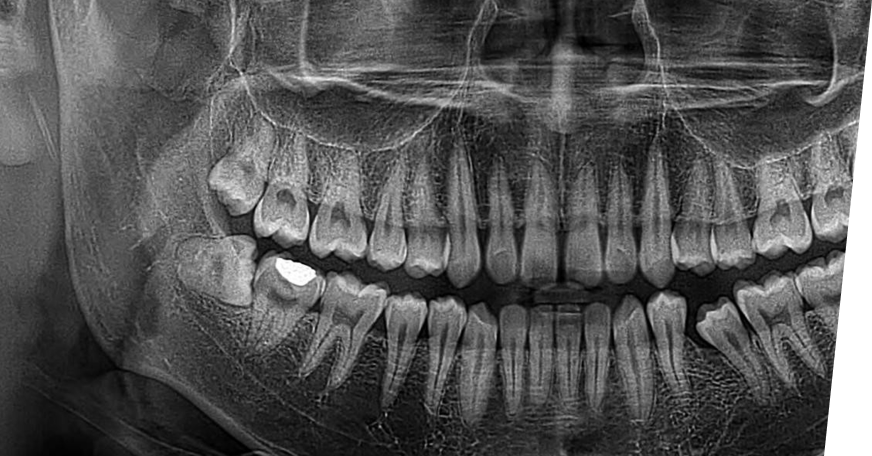

初診診察・レントゲン

撮影

まずはお口の状態を確認し、レントゲンを撮影します。必要に応じてCTも使用し、歯の生え方や神経との位置関係を確認し、安全に処置できるよう検査します。

CTによる

精密診断

CTを用いて、親知らずと神経・血管との位置関係を立体的に把握します。見えにくい部分まで正確に確認することで、リスクを抑えた安全性の高い治療計画を立てています。